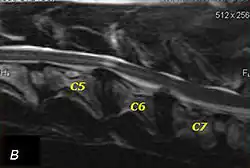

Doberman C6-C7 and C5-C6 traction responsive myelopathy B

T2 weighted MRI in neutral (A) and linear traction (B) of a seven-year-old Doberman with a two-year history of cervical pain treated with NSAIDs and presented acutely tetraplegic: A C6-C7 and C5-C6 traction responsive myelopathy are evident on MRI. The spinal-cord hyperintensity seen at the C5-C6 is suggestive of chronic lesion and most likely responsible for the chronic history of cervical pain, while the C5-C6 lesion was most likely responsible for the acute tetraplegia.